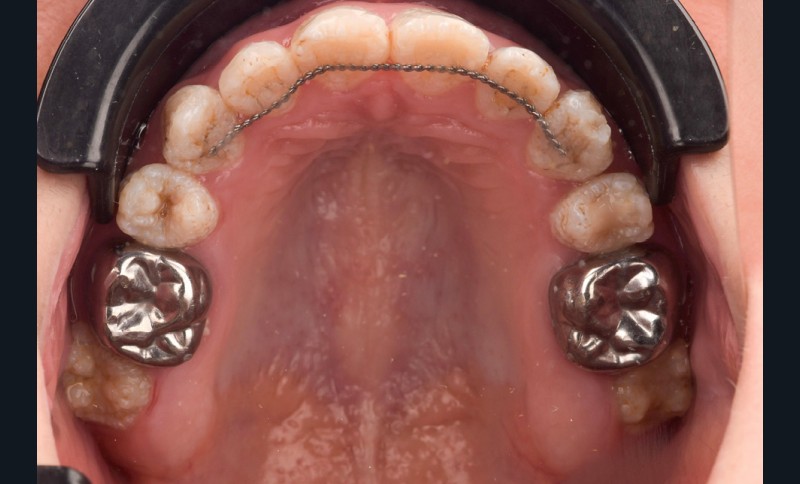

Lors de l’arrivée de la patiente, un examen clinique au fauteuil est effectué, complété par une empreinte numérique permettant l’enregistrement précis des arcades dentaires et de l’occlusion existante. Cet examen initial met en évidence une pathologie de type amélogenèse imparfaite. On note également la présence de couronnes métalliques au niveau des premières molaires, ainsi que de multiples restaurations, notamment au niveau des dernières molaires (fig. 1 à 4).